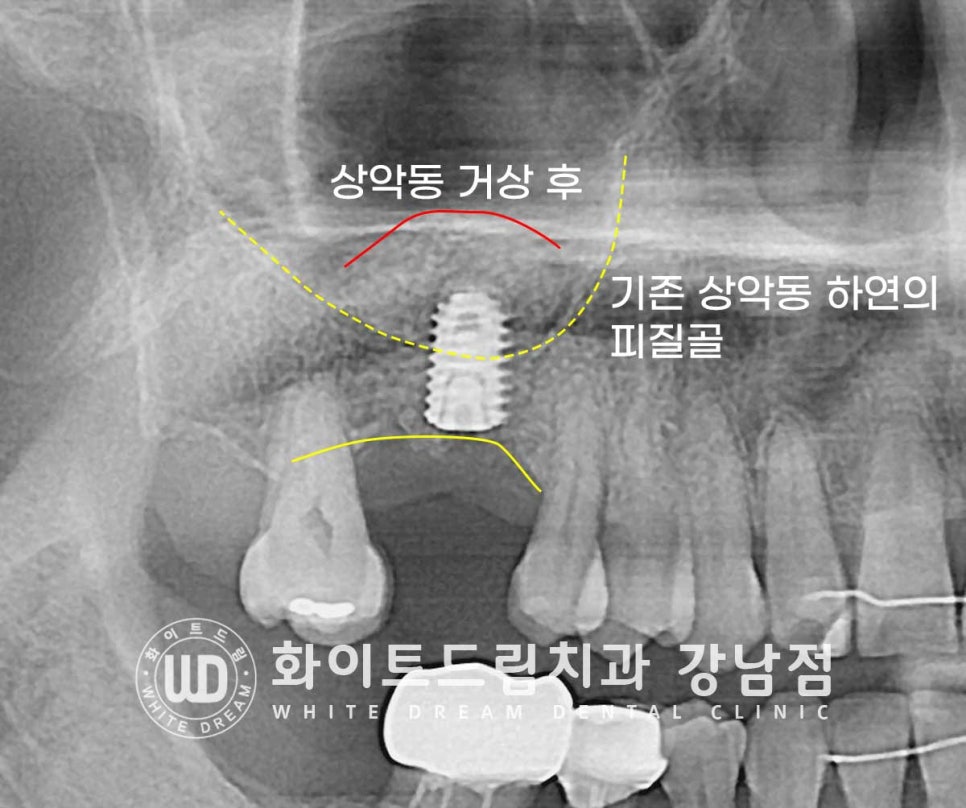

▲ 상악 어금니 임플란트 치료 / 상악동 거상술 & 임플란트 식립 : 23.04.04

오스템 CA 5.0x8.5mm 식립

그래서 잇몸뼈가 임플란트의 길이보다 부족할 경우에는

뼈이식을 동반한 상악동 거상술을 진행하게 된답니다.

※ 점막을 살짝만 들어 올릴 경우는 추가적인 뼈이식 없이 거상만 진행하는 경우도 있습니다.

환자분은 골폭 & 골 길이가 임플란트가 안정적이게

자리를 잡을 만큼 있지 않은 상태여서 많은 양의 뼈이식이 동반되어야 하는 상태였습니다.

상악동 거상 & 뼈 이식을 진행하게 되면 이렇게 x-ray 상으로

임플란트 위쪽이 하얗게 둥그런 모양으로 올라오게 됩니다.

환자분도 이 상태에서 이식재가 새로운 뼈로 형성되고, 임플란트가 새롭게 형성되는 뼈와

잘 유착될 수 있도록 5개월 동안 충분히 기다린 후 임플란트 인상채득과 보철 연결 과정을

진행하게 되었습니다.

잇몸뼈의 가장 단단한 부분을 피질골이라고 하는데

상악동을 거상한 부위에 피질골이 잘 형성되어 임플란트를 단단하게 잡아주고

상악동이 정상적으로 회복되었다는 것을 확인할 수 있습니다.